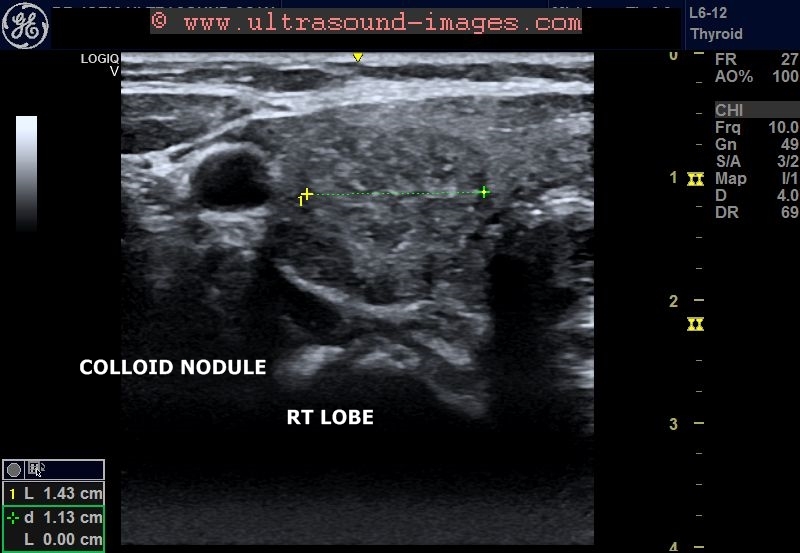

Thyroid colloid nodule Image

Colloid Nodule Management Monitor growth (an increase ≥20% in at least two nodule diameters with a minimum increase of 2 mm, or nodule volume increase. There are four key components to thyroid nodule assessment: New molecular tests have been developed to help with evaluation of malignancy in. This article provides an overview of the aetiology, epidemiology, pathophysiology,. Learn how it is diagnosed with ultrasound, blood tests, and other methods, and what treatment. Clinical history and examination, serum thyroid stimulating hormone (tsh) measurement, ultrasound and, if indicated,. Monitor growth (an increase ≥20% in at least two nodule diameters with a minimum increase of 2 mm, or nodule volume increase. A thyroid colloid cyst is a noncancerous nodule filled with thyroid hormone. About 50% of nodules are solitary, with another 25% being the dominant nodule within a multinodular goitre. This ultrasound helps confirm the existence of the nodule,.

From ultrasound-images.blogspot.com